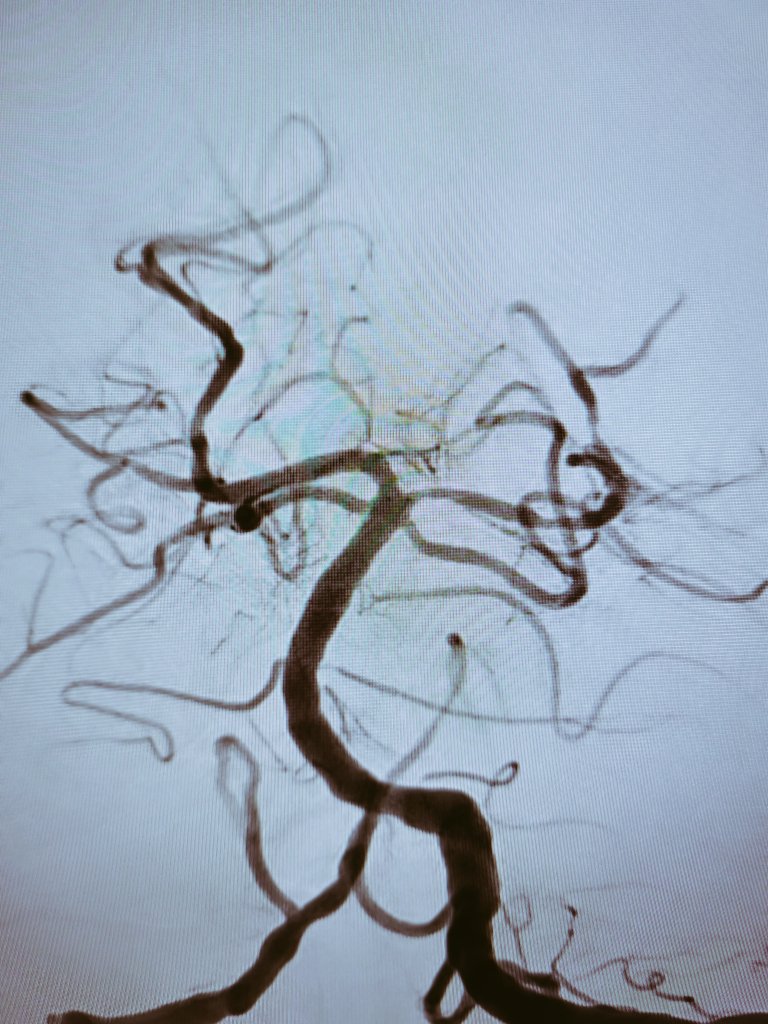

Distal M2 occlusion NiHSS 10. Complete recanalization using RED43 (@penumbrainc) aspiration catheter. NIHSS 2 at 24h.